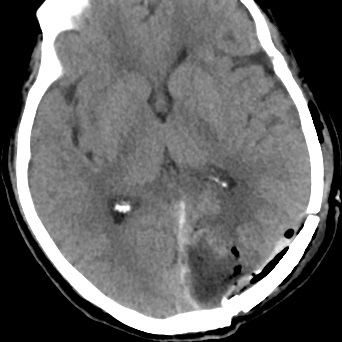

由于患者颅内占位有手术需求,肺部问题诊断又不是非常明确,我科请院麻醉科、呼吸内科、感染科、重症医学科及我院弋矶山总院神经外科专家赵心同博士就患者肺部问题、手术以及术后相关问题展开多学科会诊及讨论。

会诊中,各科主任认真阅片并分析交流,在管床医师汇报完患者相关病史后,各个学科主任相继就本科专业导向做出发言,就患者是非需要术前抗结核治疗、肺部情况是否耐受手术等做出讨论,讨论中调阅2年前患者既往我院就诊的肺部影像资料,对比本次胸部CT无明显变化,最终讨论决定积极手术治疗并做好应急预案。

经过多学科会诊及讨论后决定与家属积极沟通,考虑手术为限期手术,手术不排除增加手术风险性或者术后出血多种严重并发症,在积极完善术前准备及术后预案的情况下尽量降低手术的风险性,最终手术在弋矶山专家刘策刚主任的亲自主刀下完成,术后患者生命体征平稳,目前已康复出院。